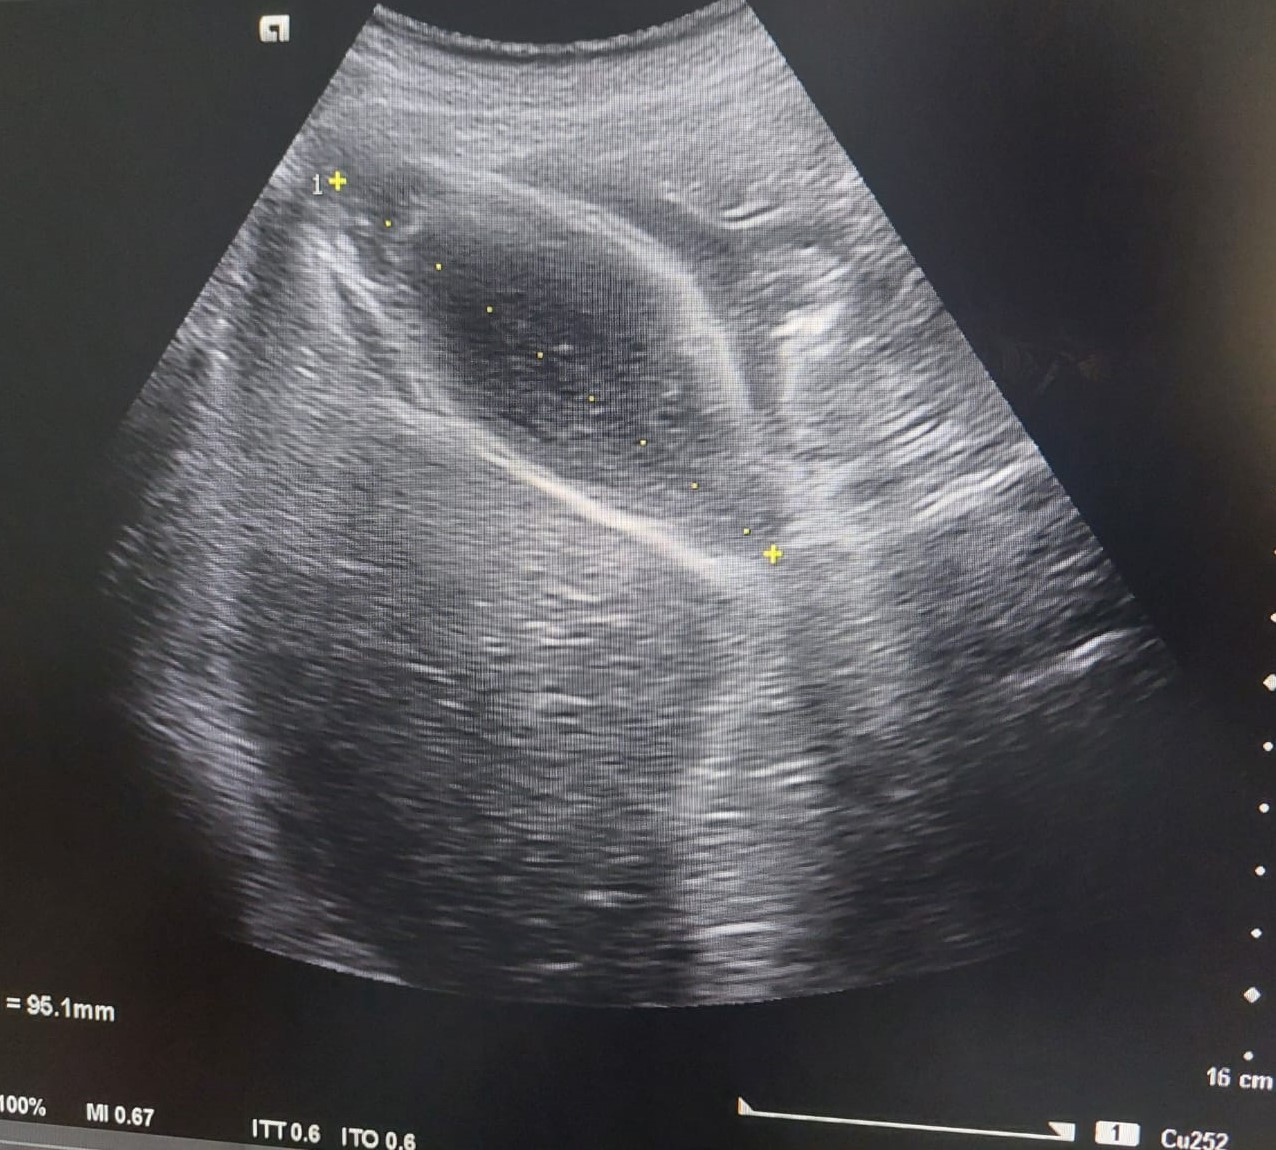

Se realiza una ecografía clínica abdominal en la que destaca un engrosamiento de la pared anterior de la vesícula biliar, sin imágenes hiperecogénicas en su interior. Parénquima hepático y riñón derecho con morfología y ecoestructura normal.

Se deriva a cirugía que solicita ecografía reglada informándola como vesícula biliar distendida, con engrosamiento marcado y limitado a la pared del fundus vesicular asociado a barro biliar. Hallazgos no concluyentes para colecistitis aguda, y podría estar en relación con adenomiomatosis del fundus asociado a barro biliar, o menos probable colecistitis subaguda.

En anatomía patológica concluyen colecistitis crónica con signos histológicos de agudización y microlitiasis adheridas en pared.